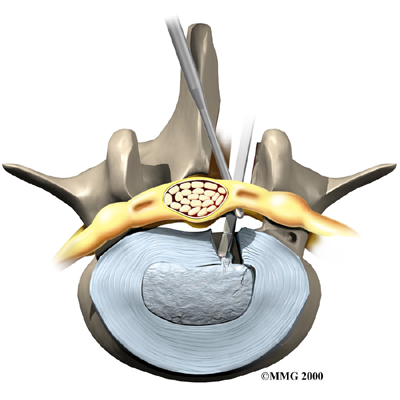

Microdiscectomy

Microdiscectomy is becoming the standard surgery for lumbar disc herniation. The procedure is used when a herniated disc is putting pressure on a nerve root. It involves carefully taking out part of the problem disc (discectomy). By performing the operation with a surgical microscope, the surgeon only needs to make a very small incision in the low back. Categorized as minimally invasive surgery, this surgery is thought to be less taxing on patients. Advocates also believe that this type of surgery is easier to perform, that it prevents scarring around the nerves and joints, and that it helps patients recover more quickly.

Related Document: FYZICAL Bridgeville's Guide to Lumbar Discectomy